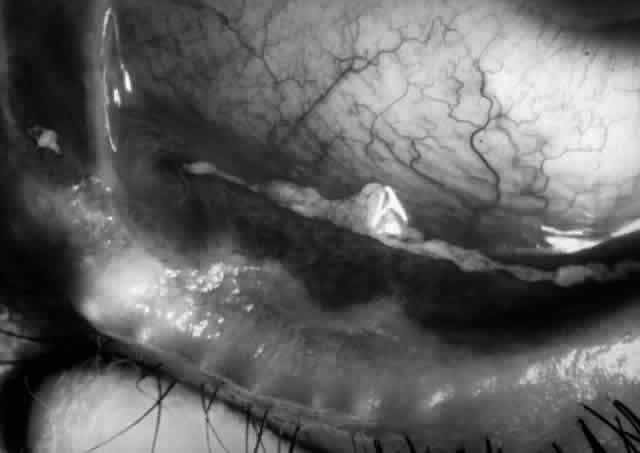

Clinically, the ocular disease in cicatricial pemphigoid (OCP) may present unilaterally in the form of a chronic, recurrent catarrhal conjunctivitis, but it eventually becomes bilateral. Subepithelial fibrosis is characteristic of stage 1 of OCP (Fig. 7). Stage 2 shows fornix foreshortening (Fig. 8), and symblepharon formation is the hallmark of stage 3 (Fig. 9). Stage 4, end-stage disease, is characterized by ankyloblepharon and surface keratinization (Fig. 10). Obstruction of the lacrimal ductules and meibomian gland ducts eventually produces an unstable tear film and progressive sicca syndrome, but it is to be emphasized that OCP is not a dry-eye syndrome until late in the disease course.20 Trichiasis and entropion occur because of the subepithelial fibrosis, with eventual keratopathy, corneal neovascularization, and corneal ulceration and scarring.20

Fig. 9. Stage 3 of an eye affected by cicatricial pemphigoid. The conjunctival “shrinkage” continued and a frank symblepharon developed.